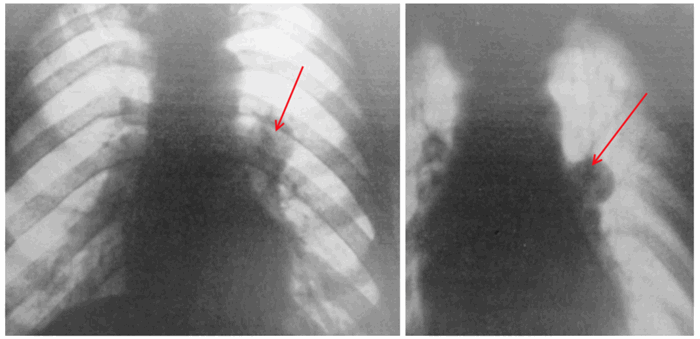

Рис. 1. Обзорная рентгенограмма грудной клетки. Стрелкой указана гамартома.

При рентгеновском исследовании обнаружено: в нижнем поле правого легкого больше кзади определяется гомогенная, округлая, четкая тень с фестончатыми контурами 3,5 см в диаметре.

Рис. 2. Хондрогамартома.

Функция внешнего дыхания не нарушена. Рентгеновское исследование. Корни уплотнены, расширены, справа на уровне 3-го ребра в медиальной зоне округлая, интенсивная, четко контурированная тень 4 см в диаметре. Она расположена ближе к задней поверхности. Синусы свободны. Границы сердца нормальны.

При рентгеновском исследовании в нижней доле левого легкого обнаружена четко контурированная округлая тень с фестончатым краем. Диаметр ее — около 3 см.